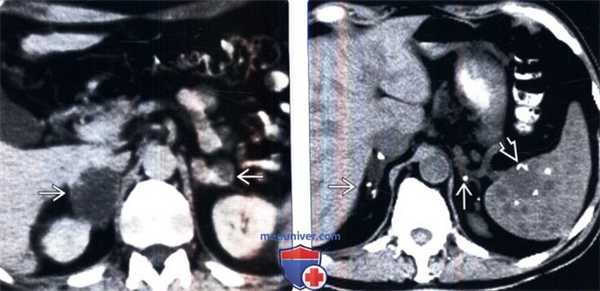

(Слева) КТ с контрастированием, аксиальная проекция: образования надпочечников с обеих сторон, в том числе одно крупное образование правого надпочечника, в котором имеются области низкой плотности вследствие некроза или дегенерации у данного пациента с острым или подострым бластомикозом.

(Справа) Бесконтрастная КТ, аксиальная проекция: очаги кальцификации в обоих надпочечниках. Обратите также внимание на кальцифицированные гранулемы, расположенные в селезенке, наряду с очагами низкой плотности, которые могут представлять собой некальцифицированные гранулемы. Данная картина может быть следствием первичного диссеминированного гистоплазмоза.